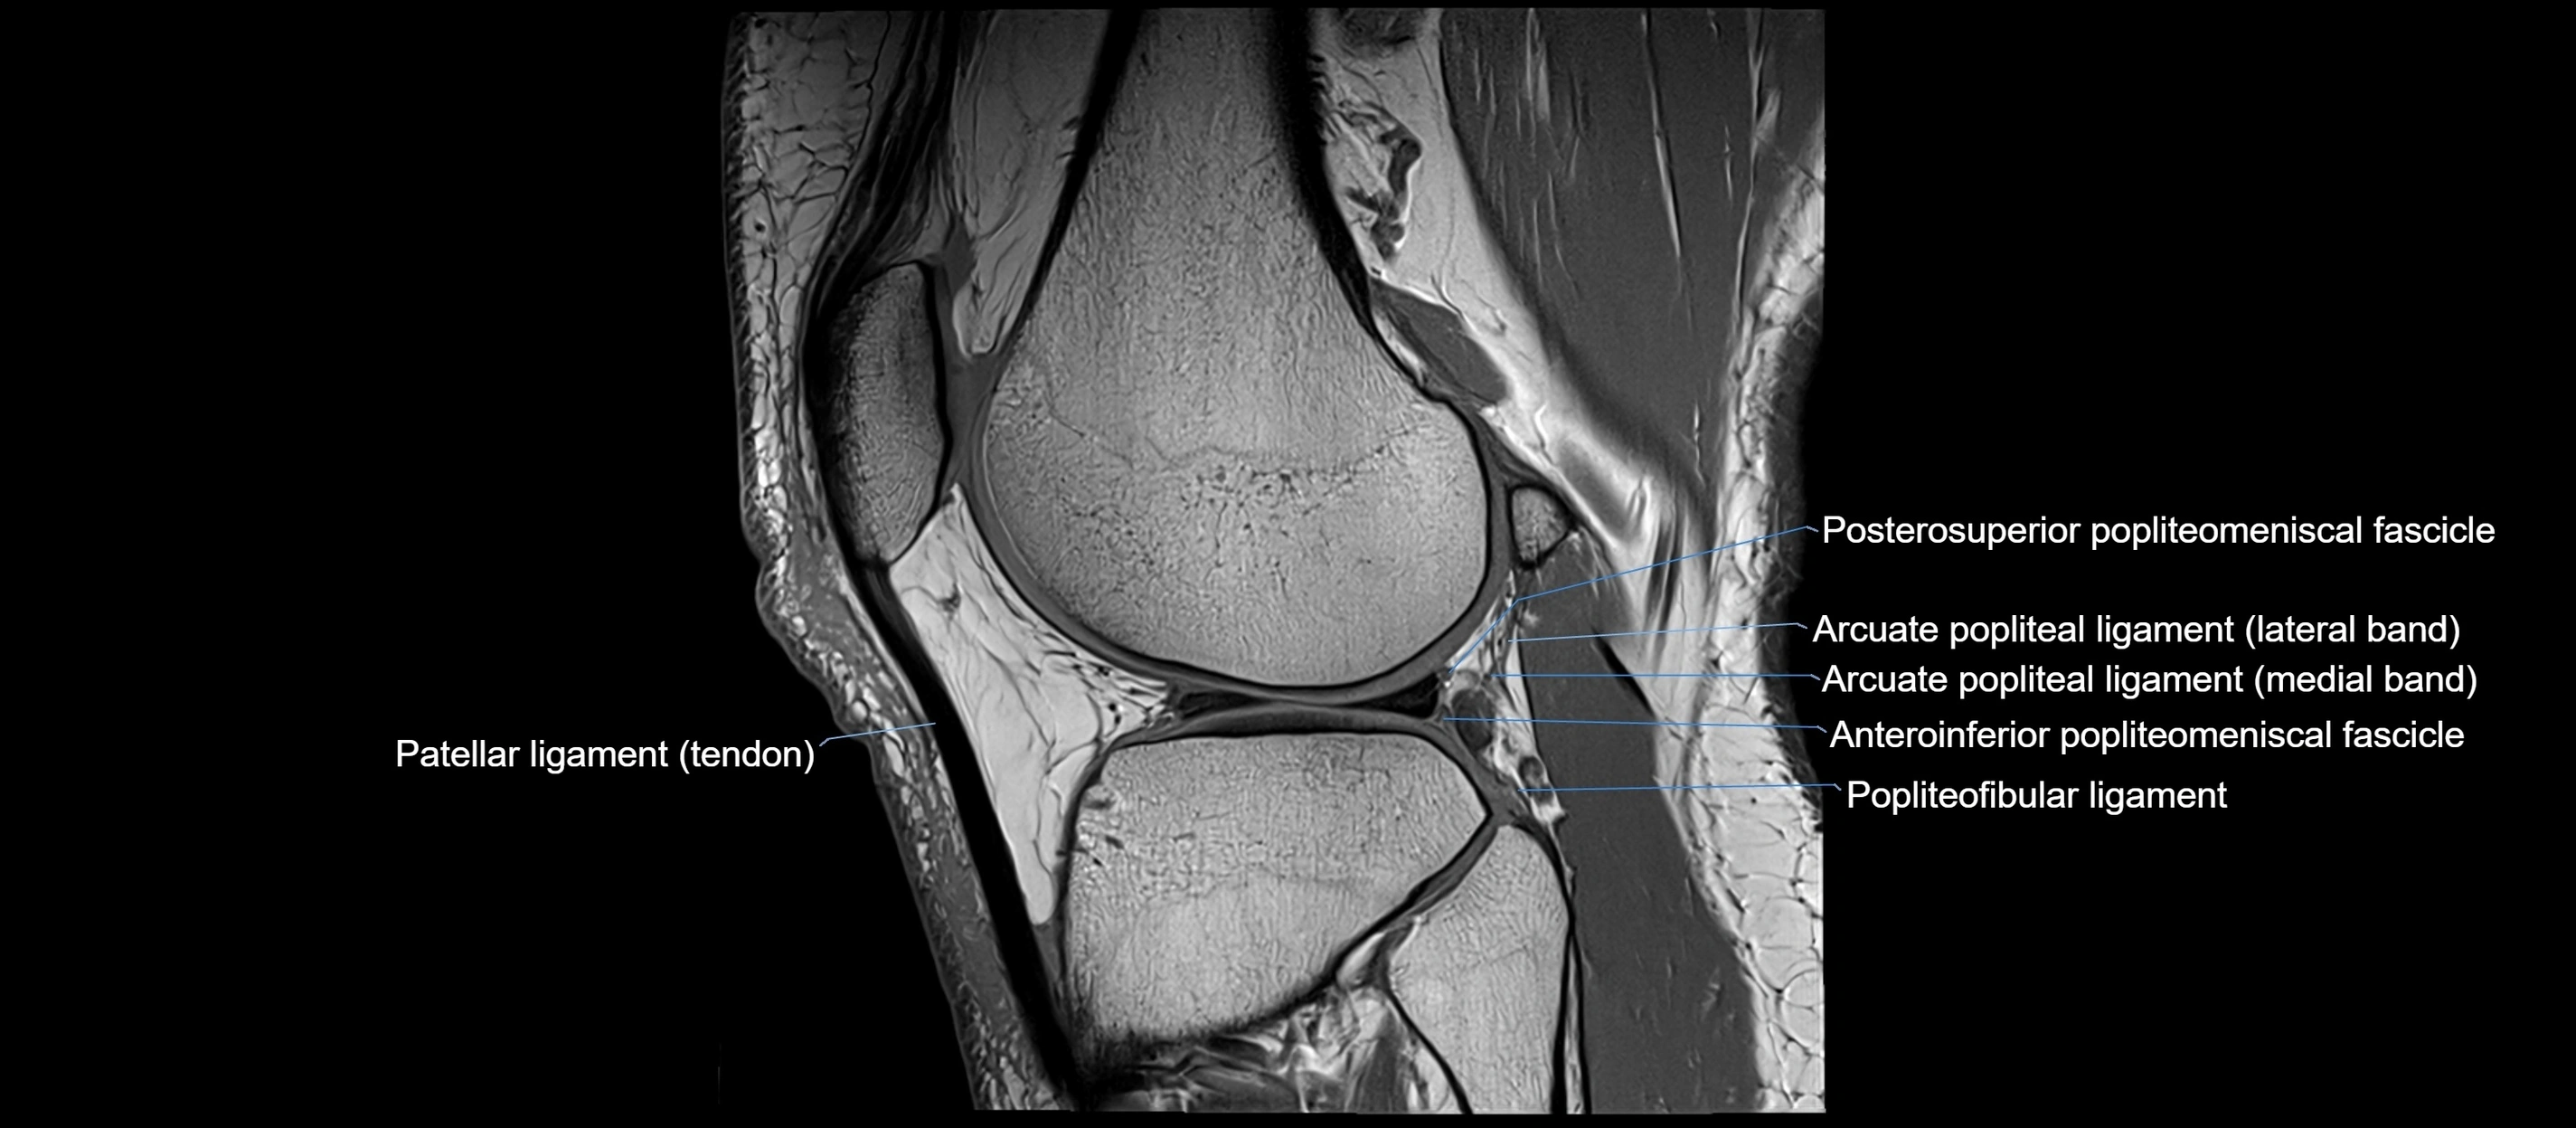

MRI images

image